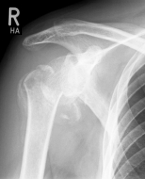

Surface replacement ("cap prosthesis" of the humeral head) in cases of mild omarthrosis and still well-preserved glenoid cavity

links: X-ray image of a cap prosthesis ("surface replacement")

right: cap prosthesis ("surface replacement", type "Durom" Fa. Zimmer)gkl